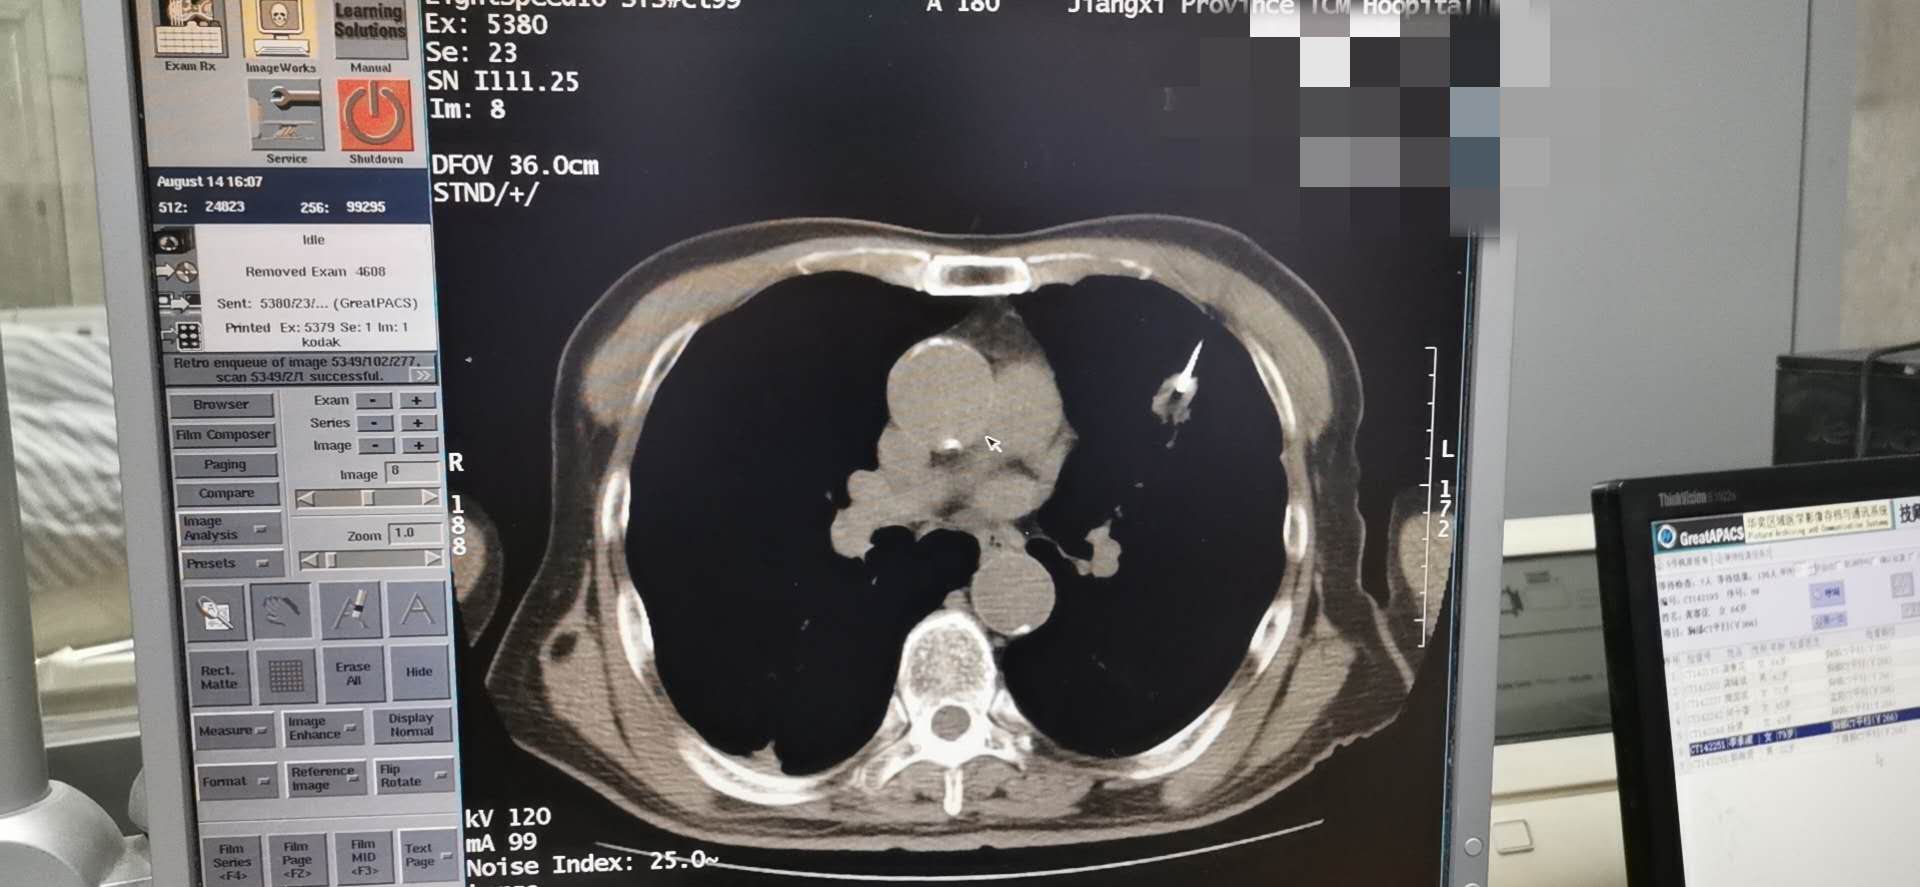

金瓶梅电影肿瘤科8.14于CT引导下完成肺穿刺术